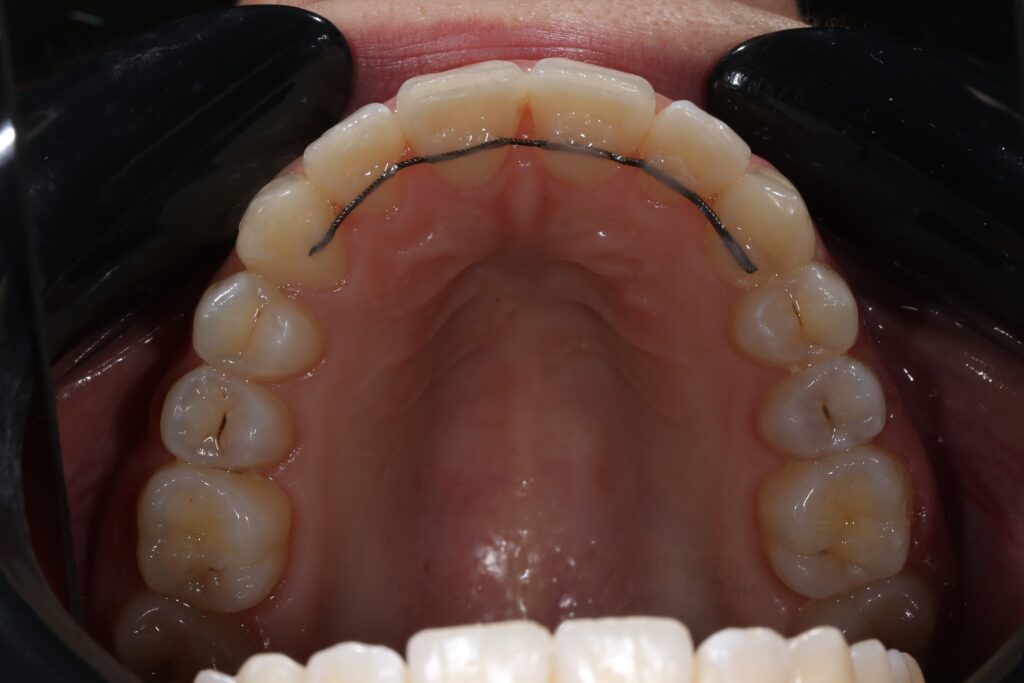

Ситуация до лечения

Жалобы: Пациентка обратилась с жалобами на неровное положение передних зубов.

Диагноз: дистальный прикус, сужение верхнего и нижнего зубных рядов, скученность фронтальной группы зубов на верхней и нижней челюсти.

пациент до лечения брекетами